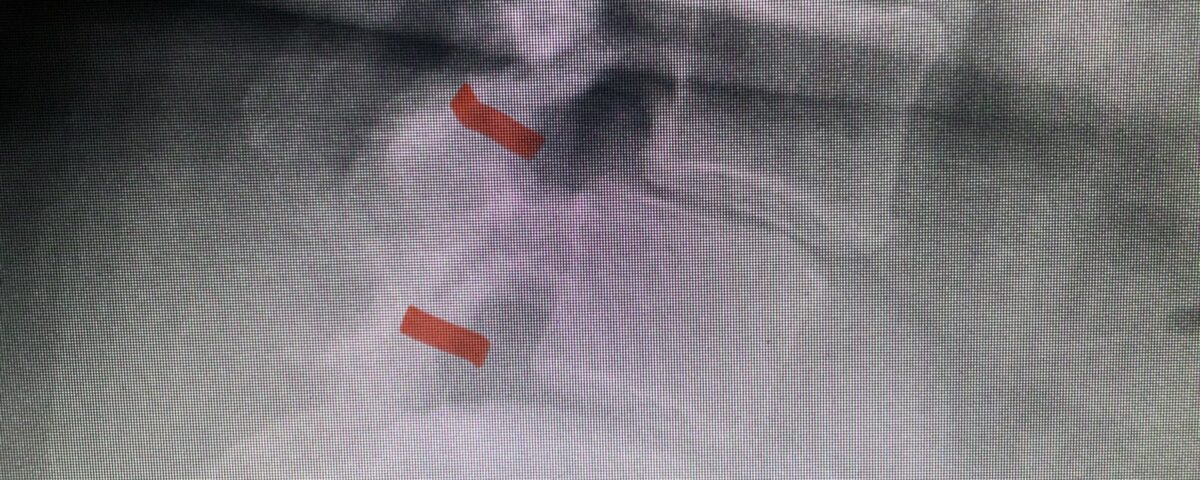

Fig 2: Lateral preoperative lumbar x-ray demonstrating L3-4 and L4-5 spondylolisthesis on flexion.